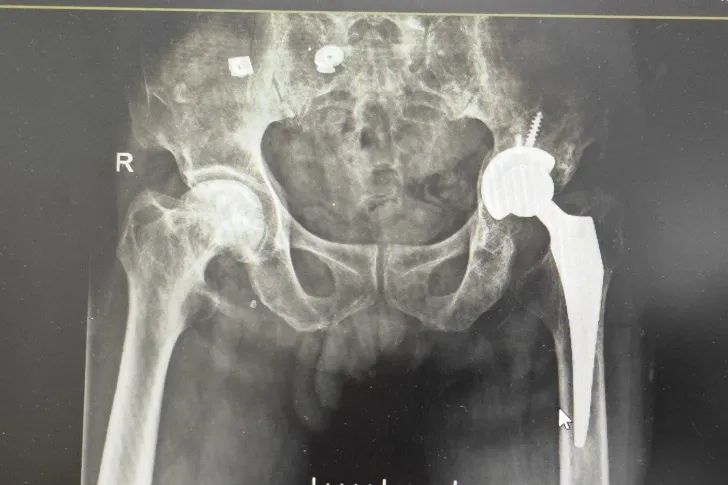

關(guān)節(jié)外科劉健安主任團隊經(jīng)認真完善輔助檢查、充分討論后,詳細制定手術(shù)計劃并成功完成了三院建院以來首臺復(fù)雜髖關(guān)節(jié)不穩(wěn)重建翻修手術(shù),術(shù)中選取愛康多孔ACT臼杯、wagner sl 股骨柄,術(shù)后患者恢復(fù)良好,假體穩(wěn)定性良好,患者非常滿意。

圖4-術(shù)后復(fù)查情況,可見關(guān)節(jié)假體穩(wěn)定性良好,位置良好